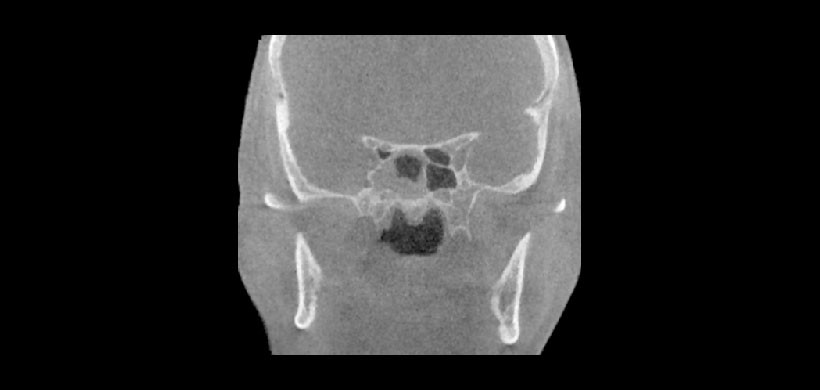

Fig 2. Tomografía volumétrica, corte coronal. Se aprecia celdilla de Haller visiblemente ocupada y el cornete medio del lado derecho invertida. Nótese contenido en el seno maxilar izquierdo.